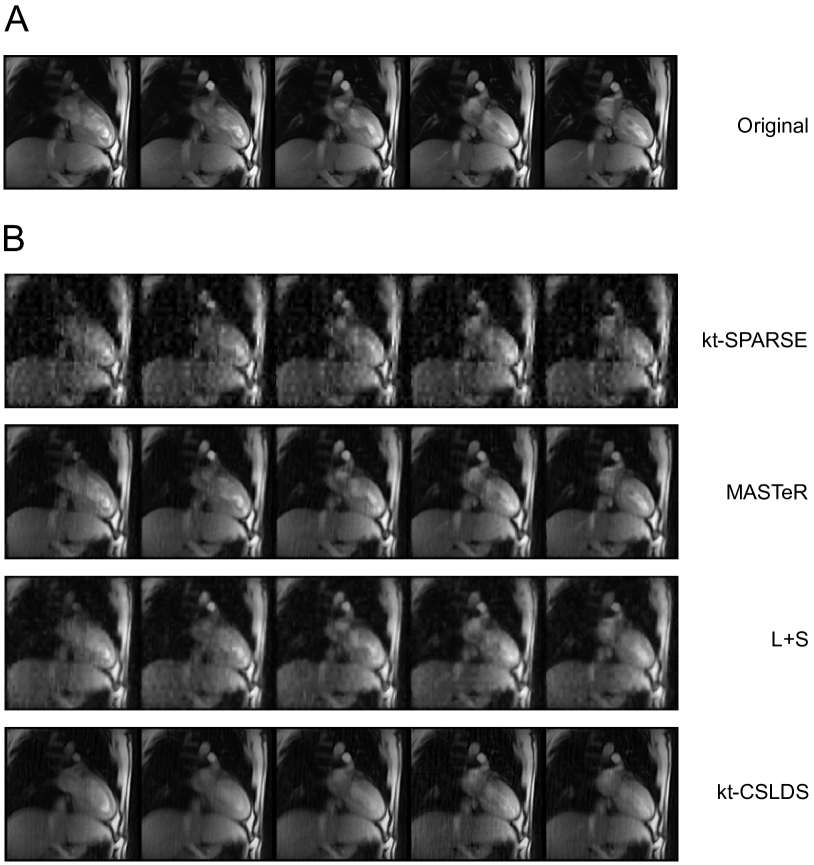

We compare kt-CSLDS with prior art in the literature, which includes kt-SPARSE, MASTeR, and L+S. Figure 8 and Figure 9 show the numerical results on two datasets described in [55]. Both datasets can be downloaded from the paper website provided by the authors. Our numerical results show that kt-CSLDS achieves excellent reconstruction quality.

Refer to caption

Figure 8: Comparison of kt-CSLDS with prior art in the literature. Numerical results are based on one dataset for dynamic heart imaging, with 1.5 mm resolution, 8 mm section thickness. The original dynamic MRI is acquired at 30 ms acquisition time with 300 frames. We downsample the heart video to 128×\times128 spatial resolution and simulate a single coil acquisition. We use 10×\times compression rate for this experiment, and employ the distance sampling strategy for compressive measurement. (A) Sample frames from the original heart video. (B) Reconstructed frames based on different video compressive sensing algorithms. Their respective reconstruction SNRs are as follows: kt-SPARSE (13.0 dB), MASTeR (18.8 dB), L+S (15.8 dB), kt-CSLDS (19.1 dB).